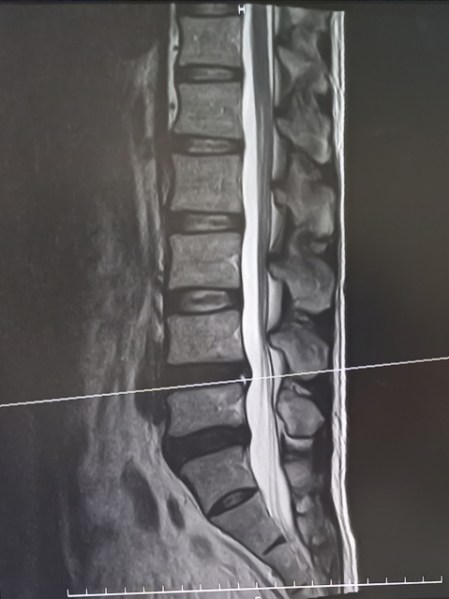

診断結果は、ヘルニアを起こしていた部分の椎間板の画像でしたから、黒くなっているところが椎間板の組織が流れ出て脊椎の神経を圧迫している部分だということで、そのため、少しでも姿勢の角度が変わると神経痛や麻痺症状が出ていたのは、ここが神経を圧迫していたからだということが判ります。

すでに当たっているので、腰を曲げることで神経を更に圧迫してしまっていたのです。